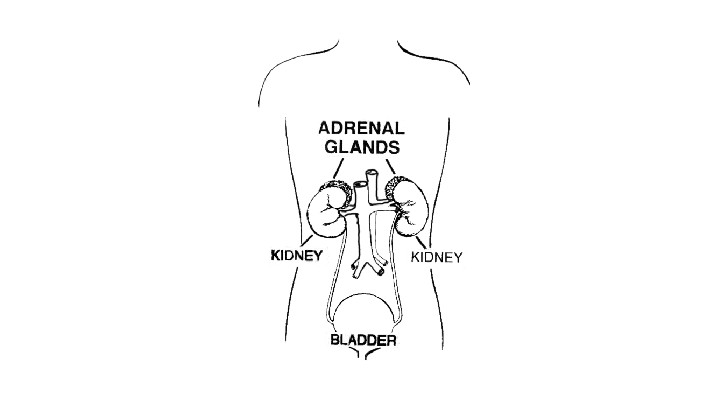

When the heart contracts, which of the following expressions describes the blood pressure that is measured?

Systolic

What is the name of the heart valves that ensure blood flows from the atria to the ventricles and not vice versa?

Atrioventricular (AV) valves

What is an embolism?

A circulating blood clot that becomes lodged in a vessel

What is an aneurysm?

A ballooning of a region of an artery